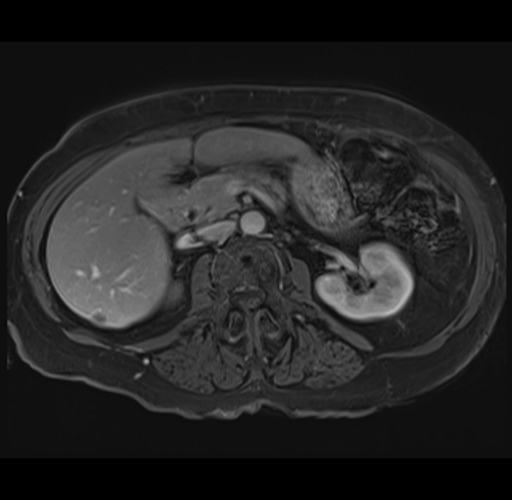

MRI T1